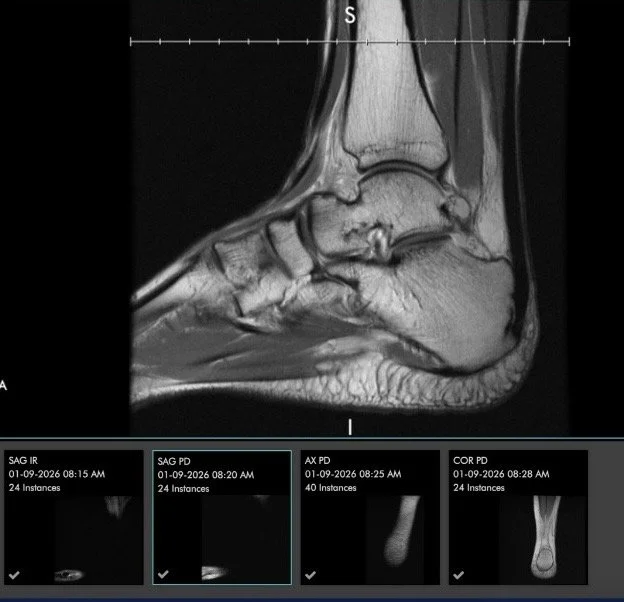

The second MRI from January 9, 2026 showed further progression:

MRI taken Jan. 9, 2026

Two torn ligaments

• Essentially full‑thickness tears of both the deep deltoid ligament and the anterior talofibular ligament

• Attenuation of the superficial deltoid ligament

• Poor scar remodeling of the calcaneofibular ligament

• No acute bone injury and no cartilage defects

These findings explained the ongoing pain, instability, and bruising I had been experiencing for over a year.